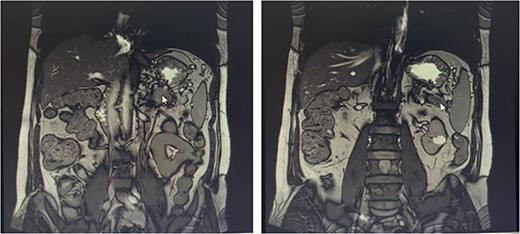

Our patient is a 55-year-old man with a history of rectal adenocarcinoma cancer in the last 2 years. At that time, he presented with flank pain and kidney stones. After examination and diagnostic tests, he was diagnosed with colon cancer that a 12 cm mass was reported and then colectomy surgery was performed. Then six sessions of radiotherapy were considered for him. In the new regression, 2 years after the colectomy surgery, during the examination phase, due to the exacerbation of pain, a computed tomogaphy (CT) scan (Figs 1 and 2) and endoscopy were requested for the patient, in which pancreatic cancer was observed. After that, the patient was placed under endoscopic ultrasound (EUS), which is reported. There was one 35 × 29 mm hypoechoic and round lesion with ill-defined border in pancreatic tail with no involvement of pancreatic duct or splenic vessels in favor of metastasis. EUS fine-needle biopsy with needle 22G was performed. Then the patient underwent a biopsy and the final confirmation was made.

Metastatic masses can be seen in the pancreatic tissue on the CT-Scan (coronal view)